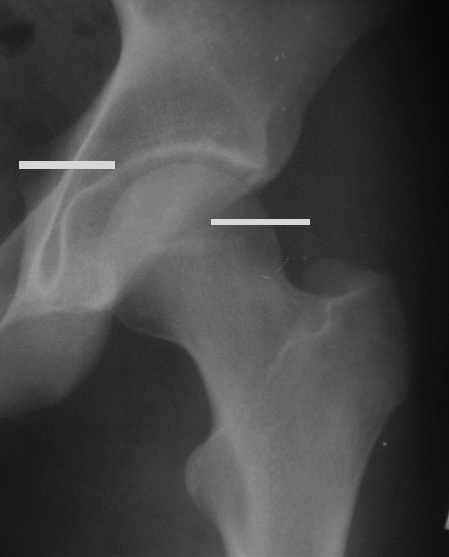

Уважаемые коллеги! Заканчивая обследование больного с переломо-вывихом бедра сделал ему обычные R-томограммы. Кажется удалось "поймать" и отломок и донорское место. Мои выводы - в скиаграмме. Считаю, что это передне-нижний фрагмент головки, образовавшийся вследствии отрывного перелома. На томограммах отломок обозначаю длинной стрелкой, а место откуда он оторвался - более короткой. Учитывая тот факт, что его размеры по КТ 25 х 15 мм считаю, что его фиксация на место необходима для профилактики артроза, что при 16-ти летнем возрасте пациента важно в плане максимального отодвигания эндопротезирования. Планирую оперировать его 24.05.05 г. Результаты представлю.

Прямой 19.05

Несколько соображений к "картинкам". На прямом снимке и КТ-томограммах все типичные линии вертлужной впадины: крыша, передняя стенка, задняя стенка - сохранены. На КТ-сканах 6 и 7 появляется фрагментация головки. С учетом R-томограмм отломок расположен спереди-снизу, а не сзади-сверху от сустава, как написано в описании КТ.